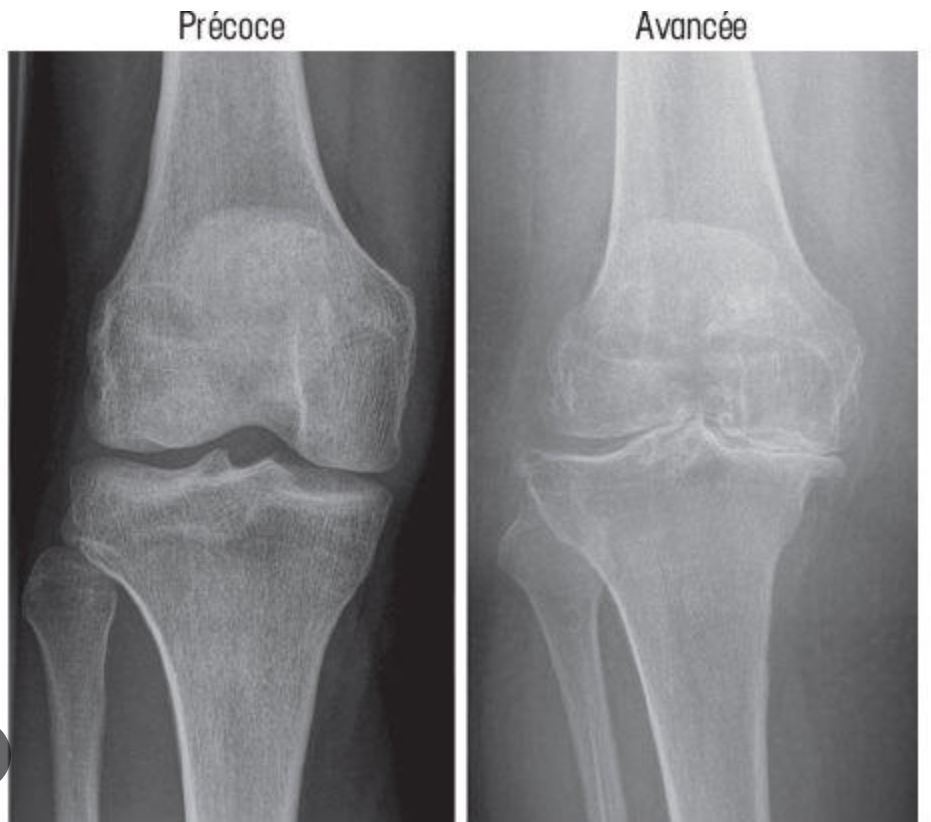

L’arthrose est une affection articulaire courante qui peut affecter les pieds, les chevilles et les genoux. En podologie, la prise en charge de l’arthrose vise généralement à soulager la douleur, à améliorer la fonctionnalité et à prévenir la progression de la maladie.